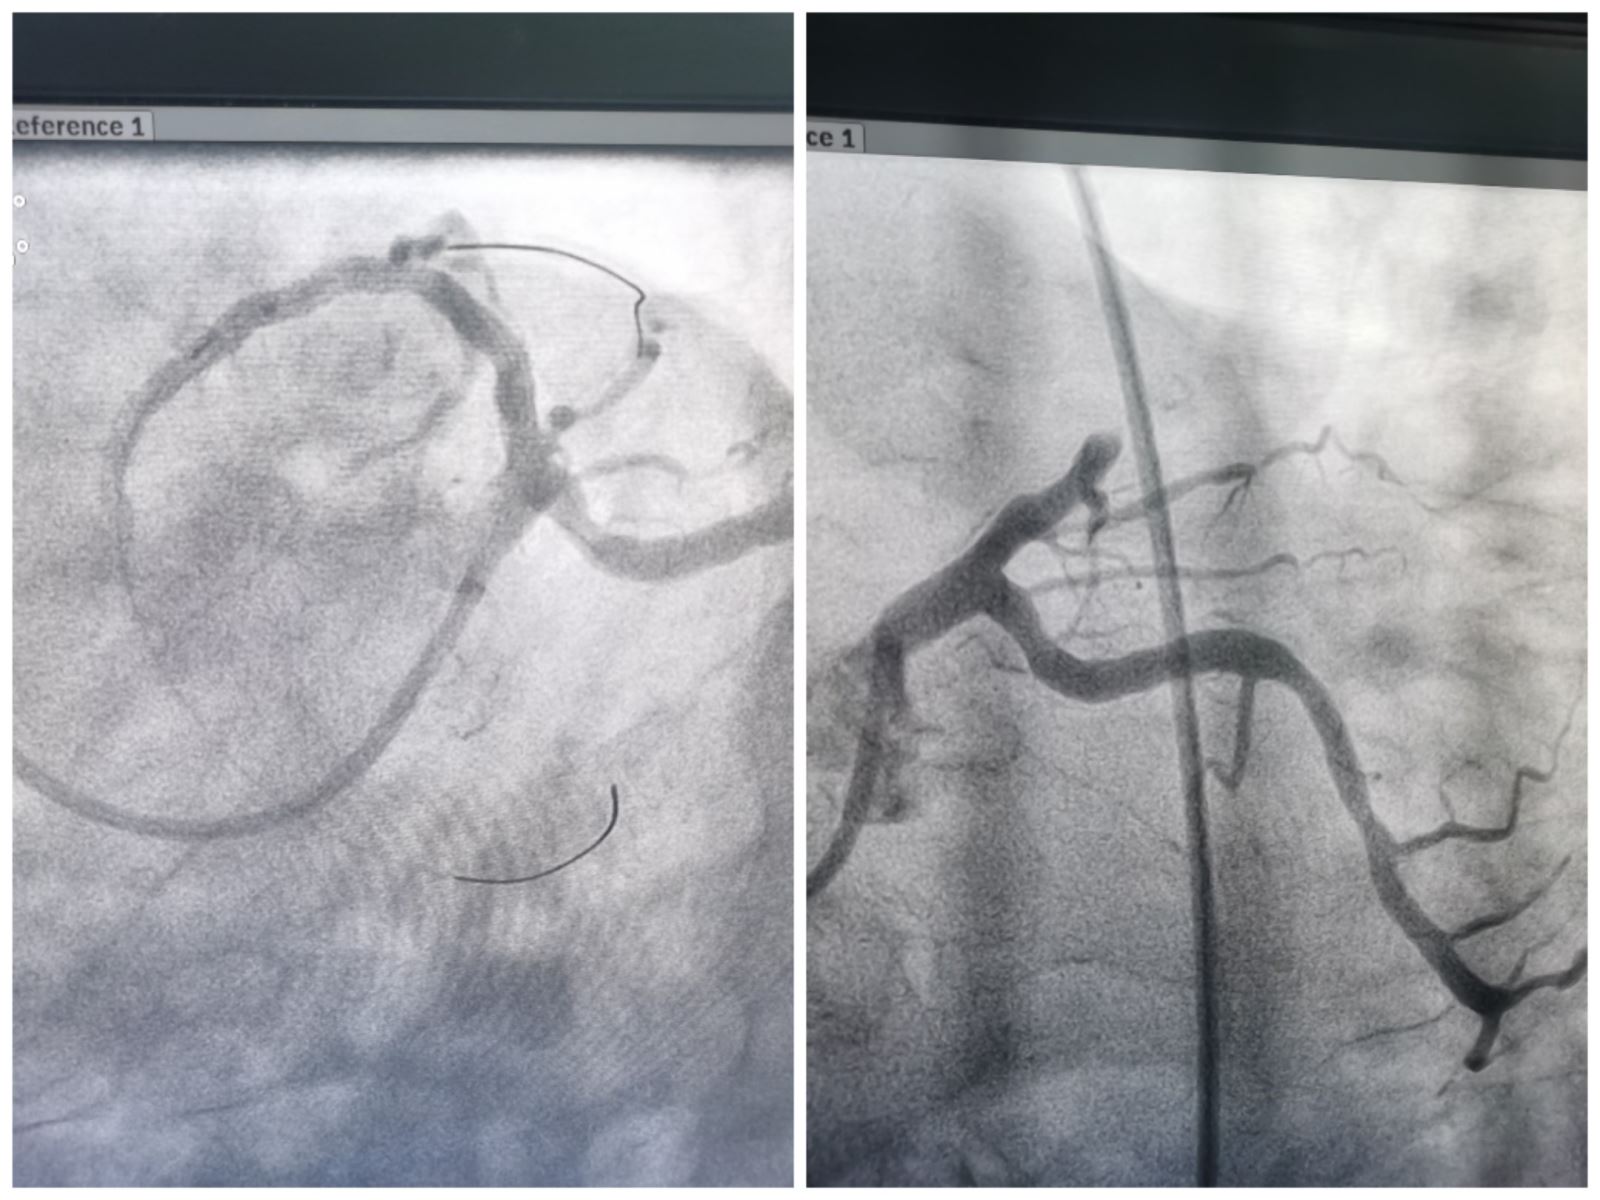

术中,胸痛中心负责人、心内三科负责人、副主任医师郑崔成,主治医师梁羽采用股动脉途径,予以行冠脉造影,造影结果显示:患者心脏冠脉病变严重,冠状动脉前降支近段闭塞,两位医生顺利通过介入方式直接开通闭塞血管,植入两枚支架,成功完成了心血管介入治疗,挽救了患者岌岌可危的心脏。随后,卒中中心团队副主任医师徐鹏、副主任医师张国锋继续采用股动脉途径,予以患者行脑血管造影,造影结果显示:脑血管前后循环大血管无明显狭窄,非取栓指征,建议内科保守治疗。经联合手术治疗后,患者胸痛、头晕、肢体无力等症状明显改善,状态良好,无不适症状。